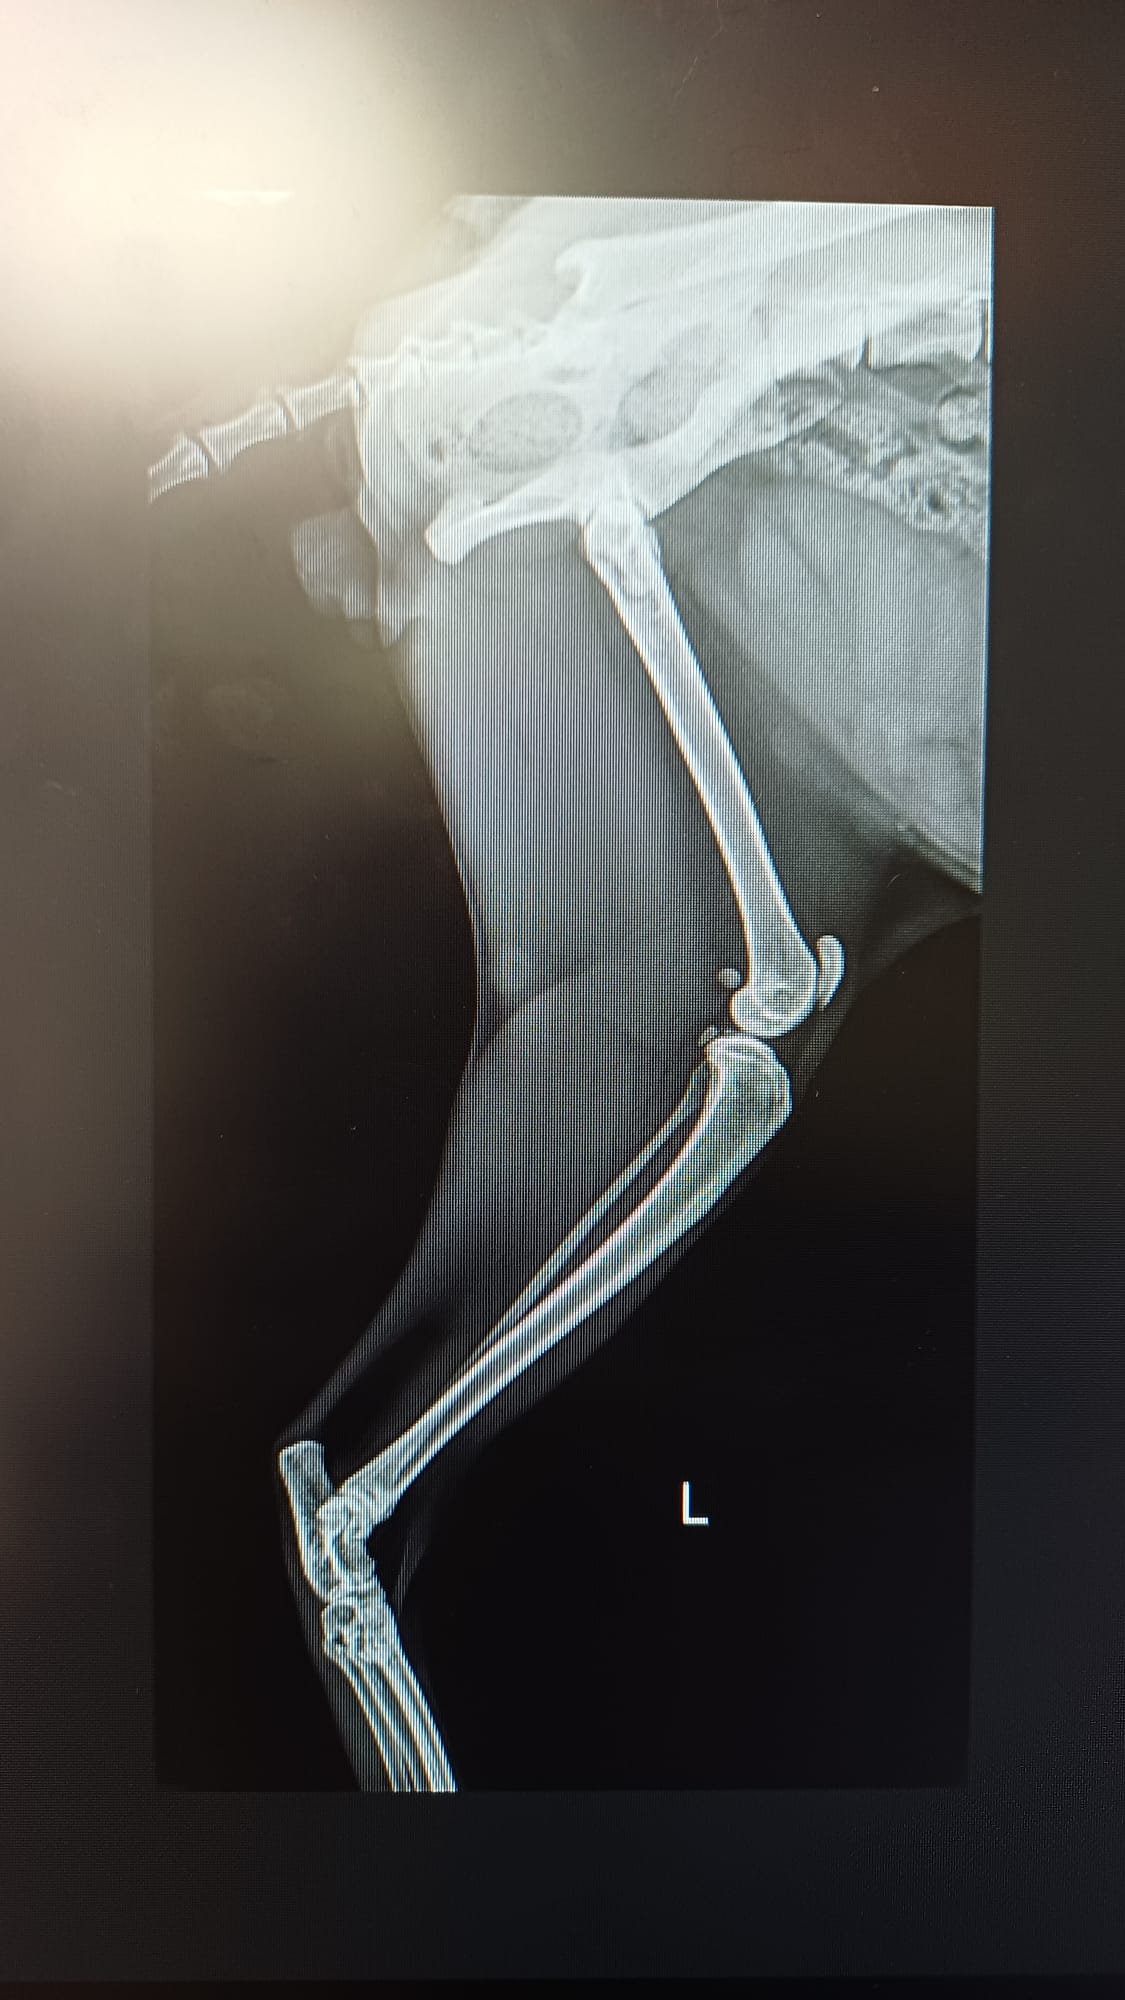

En septiembre cuando subimos a realizar las fotos del calendario vimos que no tenia masa muscular en una de las patas traseras, además de una cojera bastante importante. Nos lo llevamos a nuestros veterinarios donde se vio que tenia una Fractura antigua de la cabeza del femur. Al día siguiente se le realizo una artroplastia de la cabeza del femur. Ahora guarda reposo relativo en nuestro refugio. Es un gato adorable que nos ha robado el corazón desde el minuto 0.